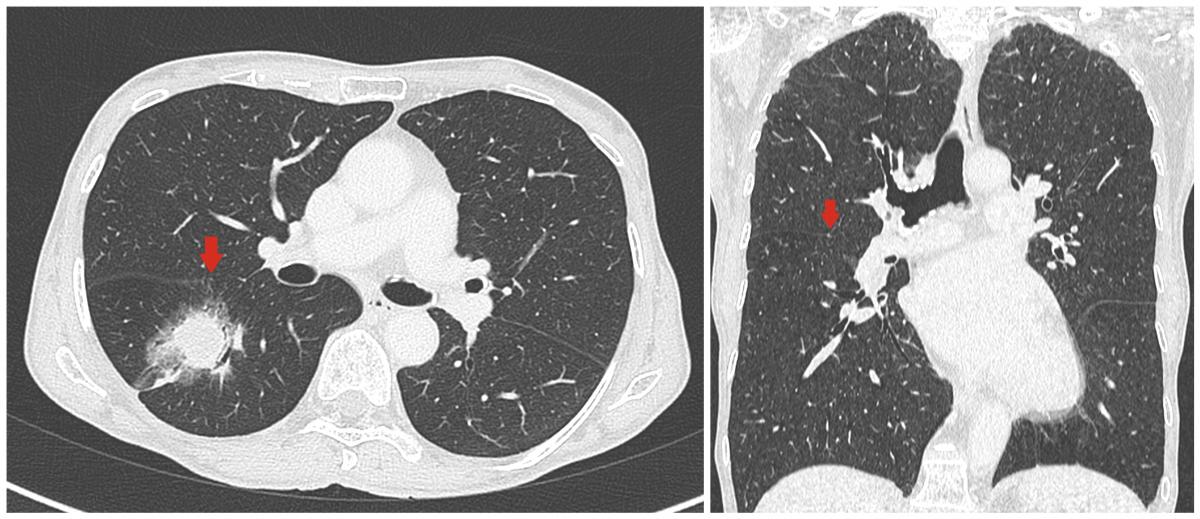

This video presents the surgical technique to perform video-assisted “hilum first–fissure last” right lower lobectomy with a two-port approach in a seventy-five-year-old female nonsmoker. The woman was admitted to an institution with a diagnosis of a 32 mm right lower lobe adenocarcinoma. The preoperative chest computerized tomography (CT) scan displayed the presence of a partially incomplete fissure. The completeness of the interlobar fissure was given the grade of 3, according to the Craig’s scale classification (Figure 1).

Figure 1: Incomplete major fissure (grade 3) showed in axial and coronal planes on preoperative CT scan.